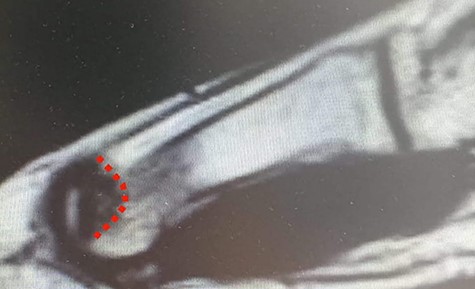

MRI of the left foot, shows low signal intensity lesion on the MH. The red dots show the depth of a subchondral cyst formation.

MRI (sagittal view) of the left foot. The red dots show a deep MH defect involving the subchondral bone, a typical finding of OD.

Standing anteroposterior (AP), oblique and lateral radiographs of the affected foot were taken. On the AP and oblique views, an OD lesion of the 1st MH was visible (lytic lesion of the subchondral bone and subchondral sclerosis formation) with a lateral-forming osteophyte (Fig. 1A and B). Magnetic resonance imaging (MRI) of the left foot clearly shows the osteochondral defect of the 1st MH (Figs 2 and 3).